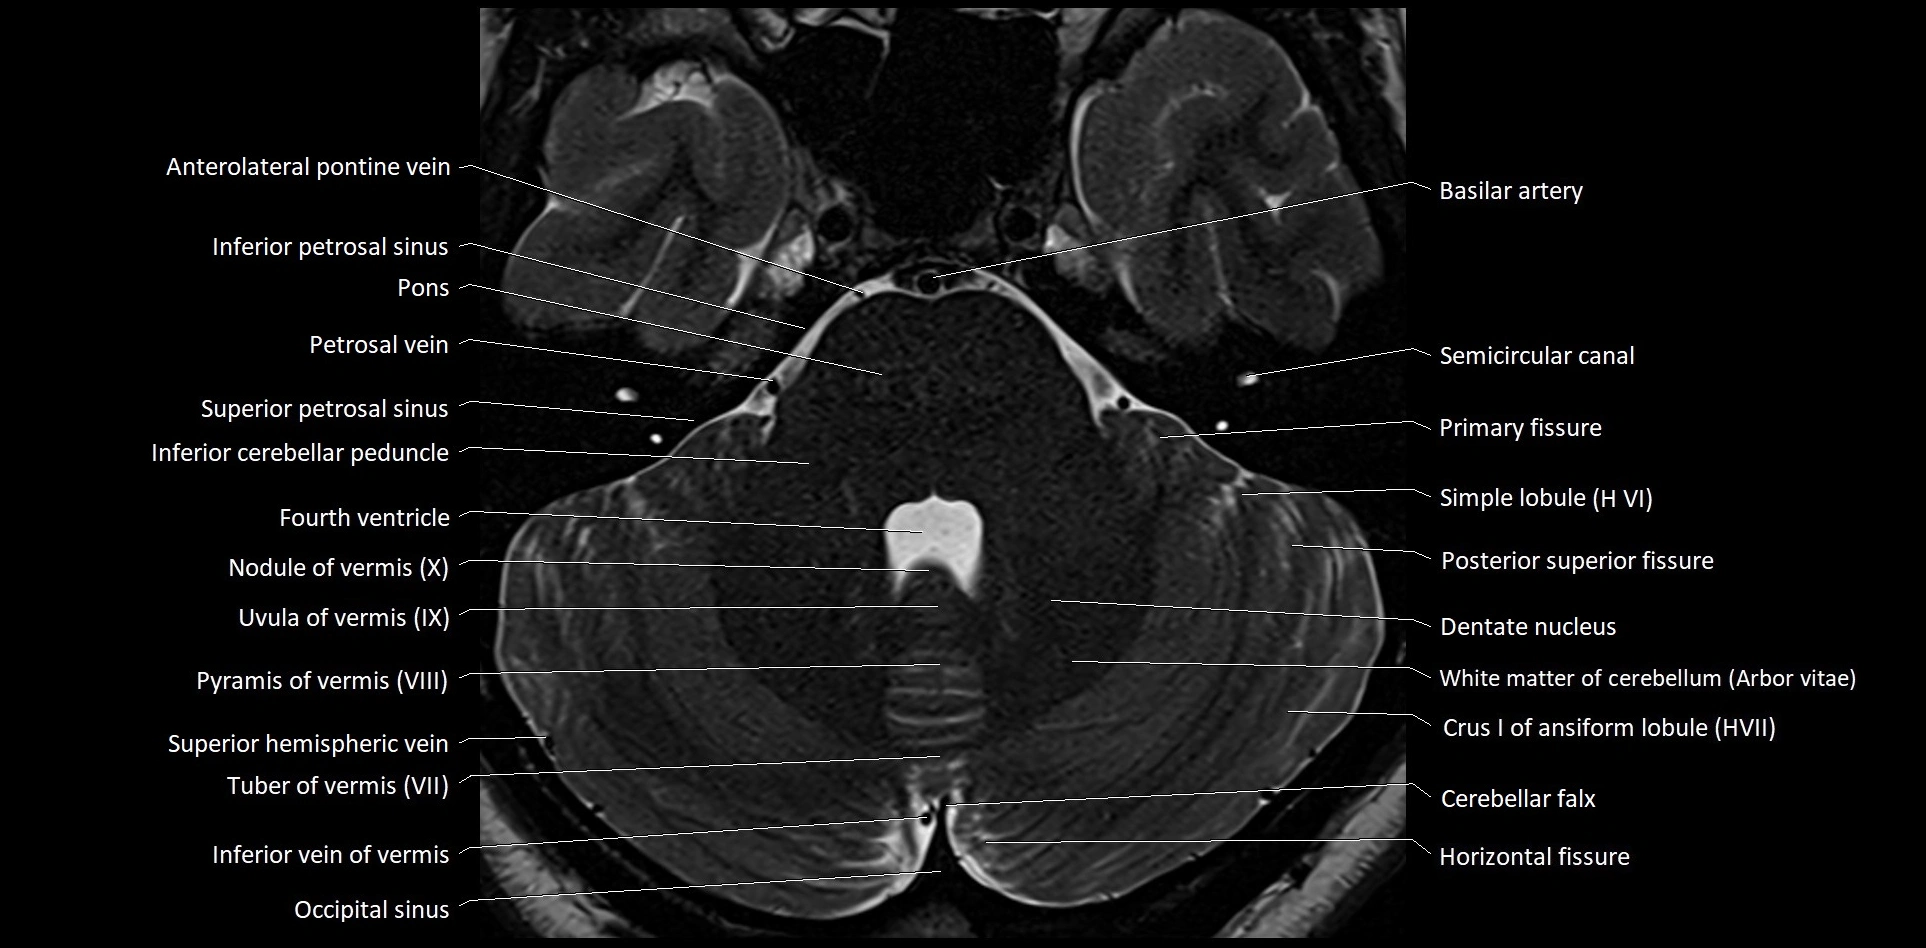

- Anterolateral pontine vein

- Arbor Vitae (Cerebellar White Matter)

- Cerebellar falx

- Dentate nucleus

- Horizontal fissure (cerebellum)

- Inferior cerebellar peduncle

- Inferior petrosal sinus

- Inferior vein of vermis

- Nodule of vermis

- Nodule of vermis (X)

- Occipital sinus

- Posterior superior fissure

- Primary fissure

- Pyramid of vermis (VIII)

- Pyramis of vermis

- Semicircular Canals

- Simple lobule

- Simple lobule (HVI) of cerebellum

- Superior petrosal sinus

- Transverse sinus

- Uvula of vermis (IX)

- White matter of cerebellum (Arbor vitae)